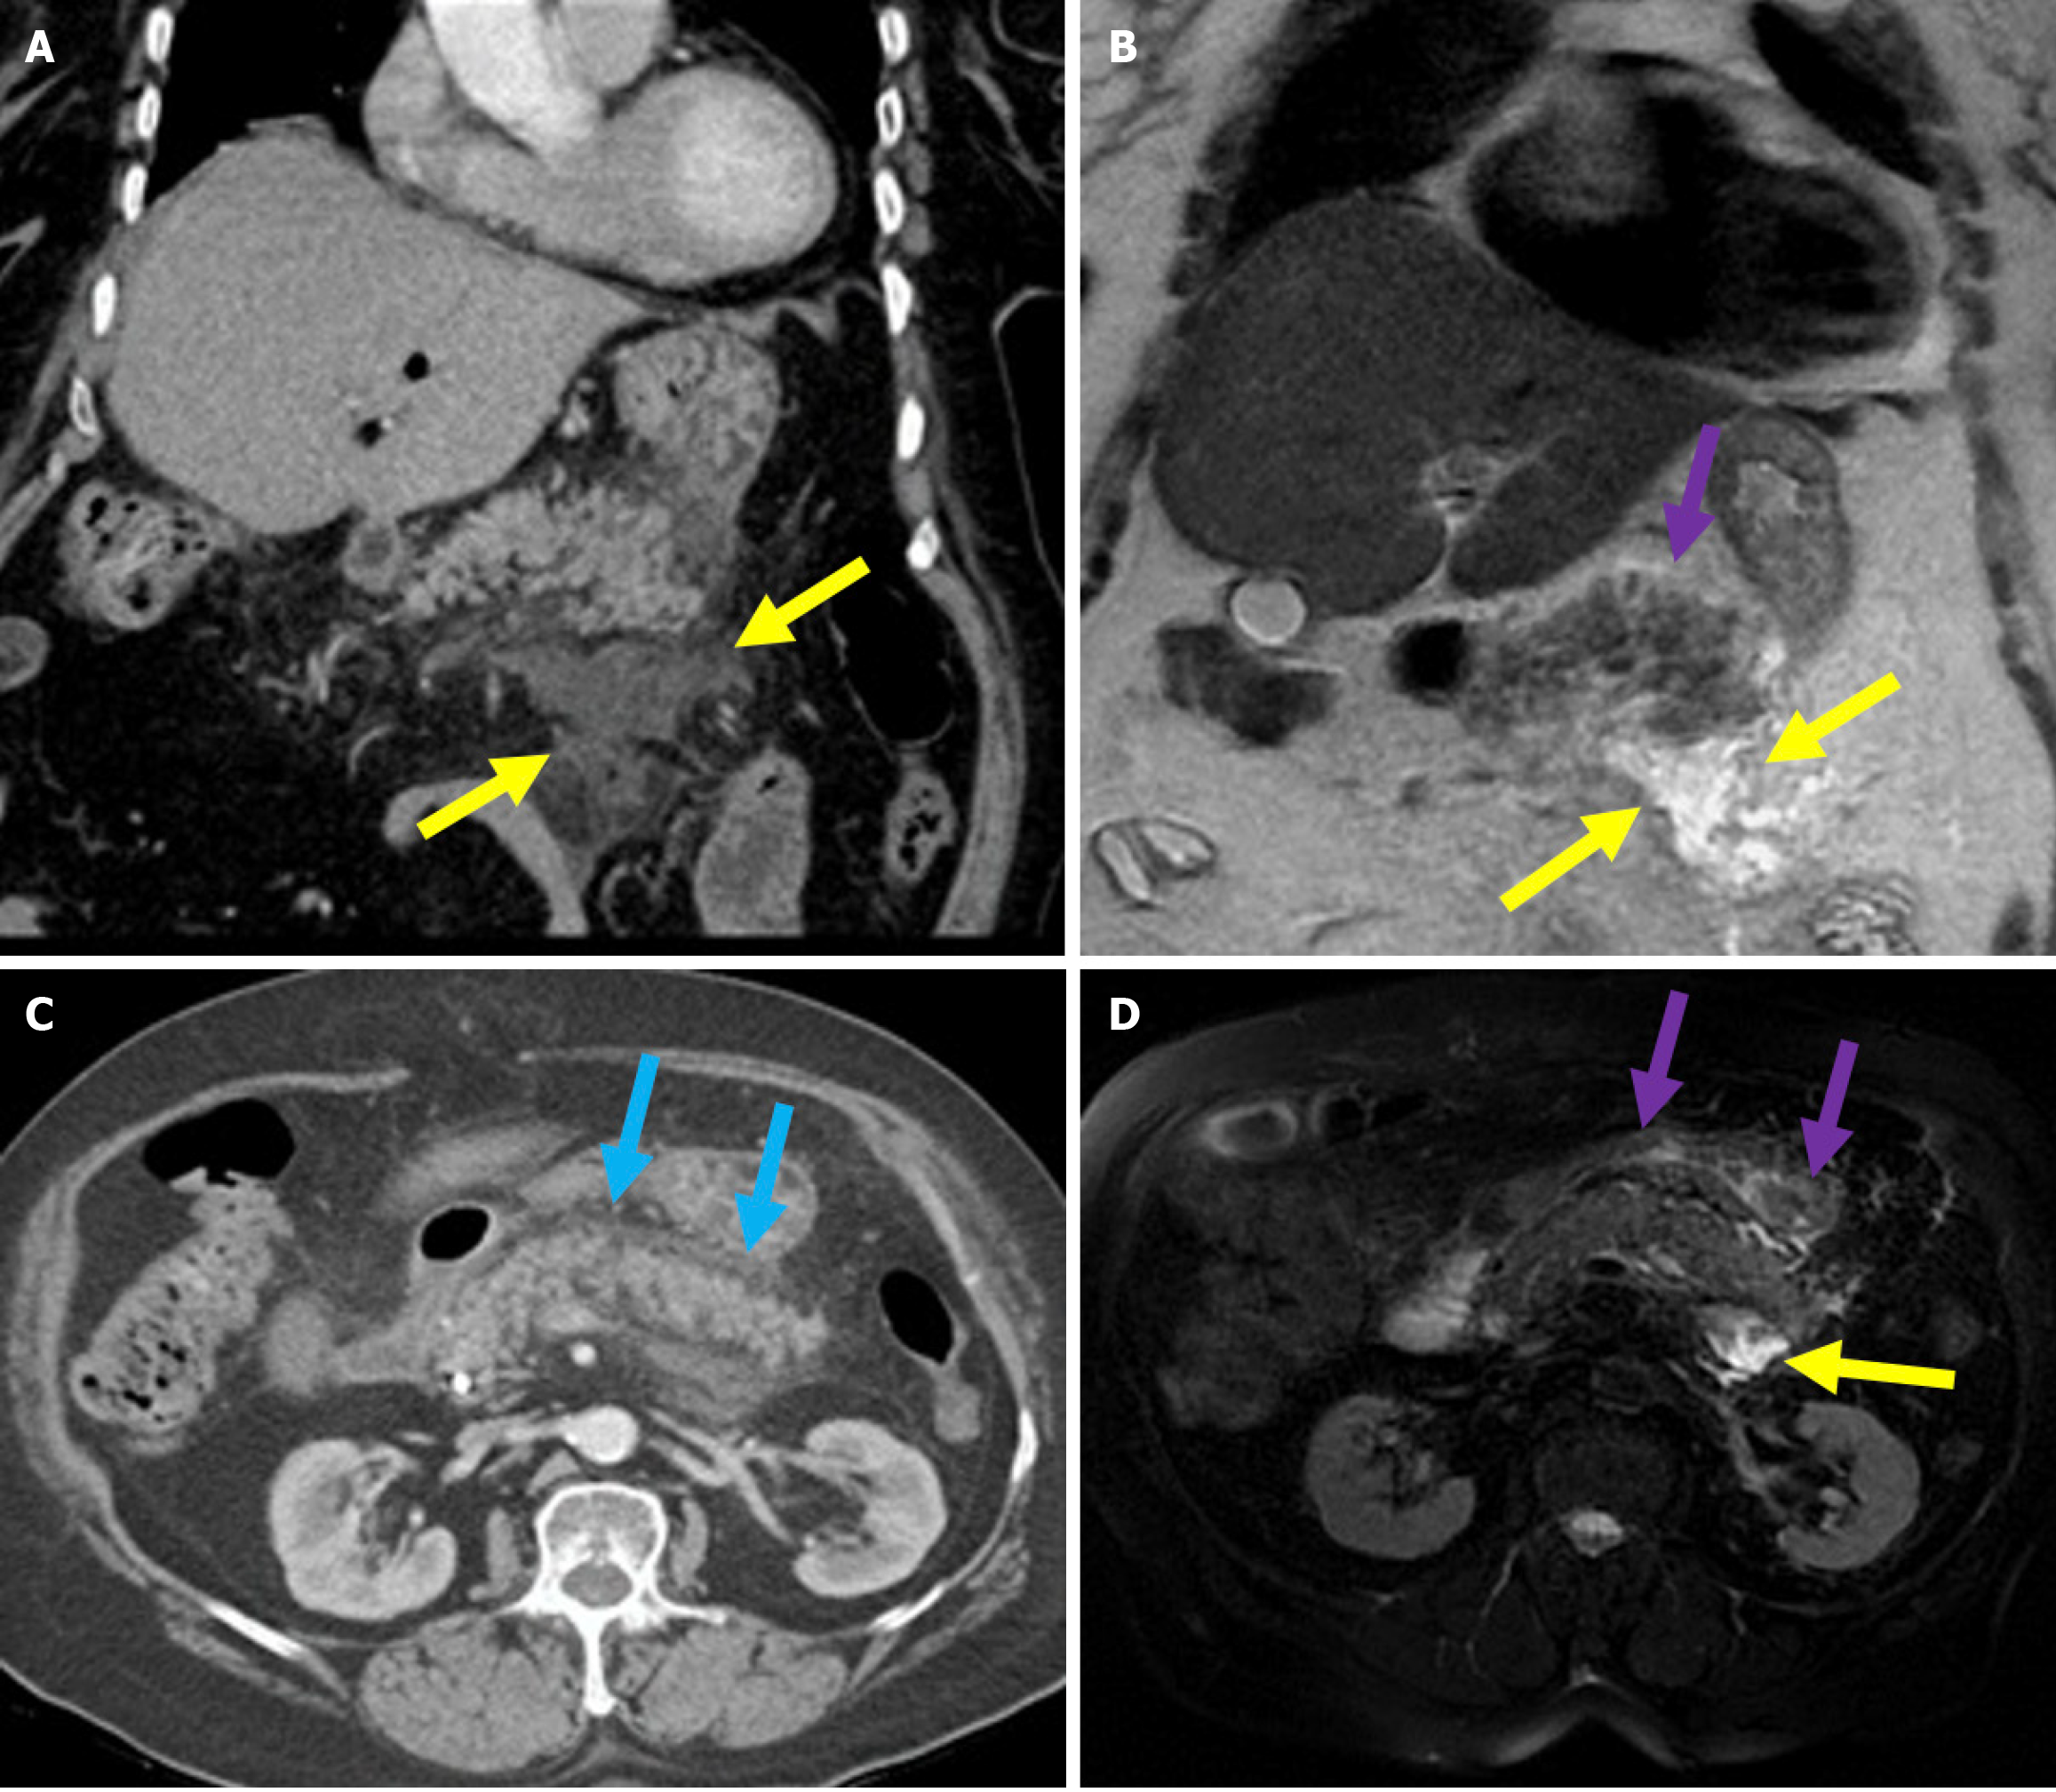

The revised Atlanta classification recognizes two primary forms of acute pancreatitis: NP and interstitial edematous pancreatitis (IEP). NP tends to follow a more severe clinical course with higher rates of infection, organ failure, and mortality. Imaging reveals hypoperfused or non-enhancing areas indicating NP or peripancreatic necrosis. Early collections (within 4 weeks) are referred to as acute necrotic collections. Once encapsulated after 4 weeks, they are known as walled-off necrosis (Figure 3)[23]. IEP is characterized by a diffusely enlarged pancreas with homogeneous enhancement on CECT imaging without areas of necrosis and with peripancreatic fat stranding and fluid accumulation. Fluid collections observed within the first 4 weeks are termed acute peripancreatic fluid collections, while those persisting beyond 4 weeks are classified as pancreatic pseudocysts (Figures 4 and 5).

Figure 3

Figure 3 Necrotizing pancreatitis, acute necrotic collections, and walled-off necrosis. A and B: Contrast-enhanced axial computed tomography (CT); C: T2-weighted magnetic resonance imaging (MRI); D: Post-contrast fat-suppressed T1-weighted MRI. A 76-year-old male patient underwent endoscopic retrograde cholangiopancreatography due to choledocholithiasis. On the evening of the procedure, the patient developed acute abdominal pain that was unresponsive to analgesics. Laboratory tests revealed elevated levels of aspartate aminotransferase, alanine aminotransferase, and lipase. Within the following 24 hours, the patient’s condition deteriorated and developed into shock. Subsequently, the patient required vasopressor support and intubation. Contrast-enhanced CT (A and B) was performed due to the severe abdominal pain. The images showed a markedly enlarged pancreas with areas of non-enhancement consistent with necrotizing pancreatitis that was accompanied by peripancreatic edema (yellow arrows). Heterogeneous acute necrotic collections were also observed in the peripancreatic region (blue arrows). Two months later, an MRI was performed for follow-up. On T2-weighted images (C) a collection with a heterogeneous internal structure and defined wall that was consistent with walled-off necrosis was visualized (orange double-sided arrow). There was a significant loss of pancreatic volume due to necrosis. In the post-contrast T1-weighted fat-suppressed image (D), contrast enhancement of the wall of the collection was noted. A small remnant of pancreatic tissue with normal contrast enhancement was observed (purple arrow).

MRI with its superior soft tissue resolution offers greater accuracy for the assessment of small necrotic regions of the pancreas[33]. Although MRI is less accessible and more costly than CT, it can be used for the diagnosis and follow-up of PEP. In IEP, pancreatic enhancement is preserved, and T2-weighted images typically reveal increased signal intensity, indicating pancreatic edema and peripancreatic inflammatory changes including fat stranding and fluid collections. In NP, decreased or heterogeneous enhancement areas are seen (Figure 3)[33]. In 20% of patients with NP, necrosis is confined to the peripancreatic fat without involvement of the pancreatic parenchyma. Patients in this category usually experience a more favorable disease course compared with those with glandular necrosis but a worse outcome than in individuals with IEP[34]. MRI is superior to CT in evaluating peripancreatic fat necrosis due to its enhanced soft tissue contrast[35]. MRI and MRCP are particularly valuable in visualizing the communication between pancreatic ducts and fluid collections. They aid in the diagnosis of disconnected pancreatic duct syndrome and determining the need for surgical intervention[33,35,36].